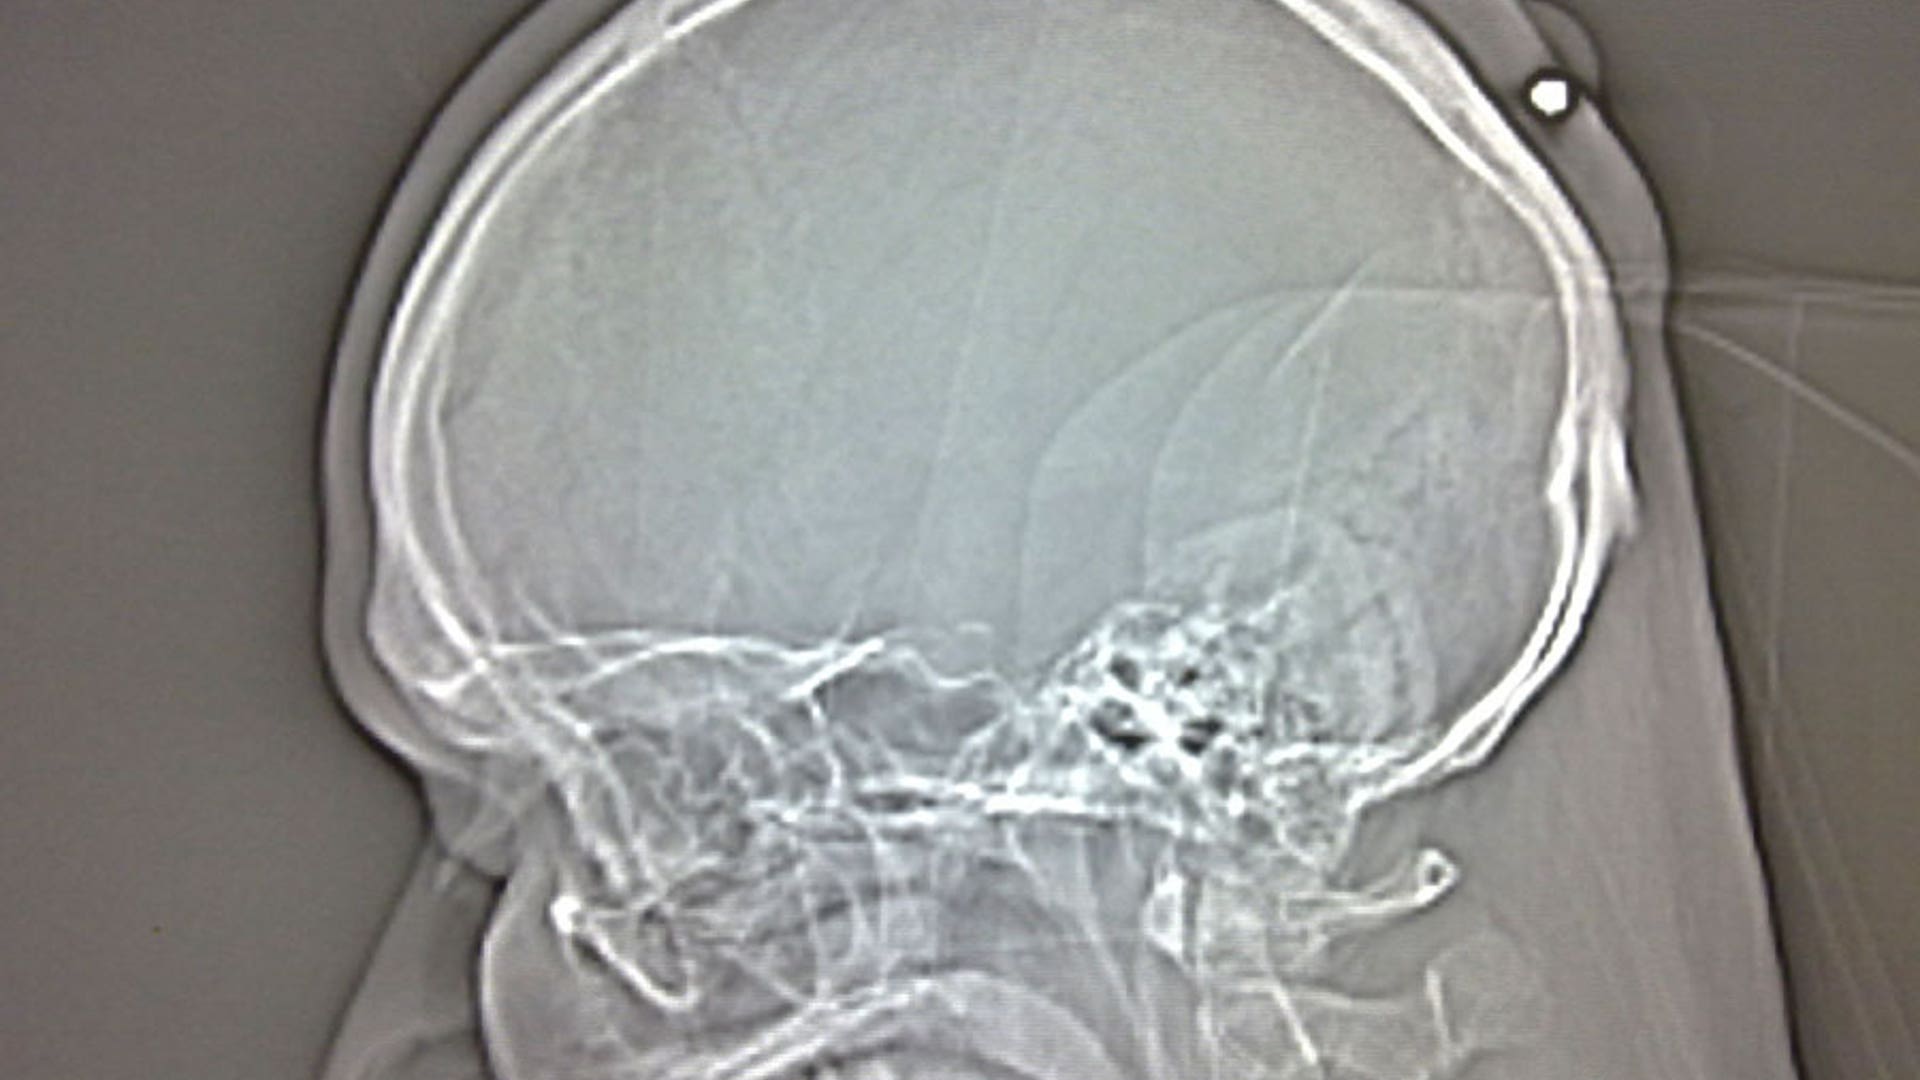

A U.S. military doctor removed a live round of ammunition from the head of an Afghan soldier in an unusual and harrowing surgery. Doctors say a 14.5 millimeter unexploded round — more than 2 inches long — was removed from the scalp of an Afghan National Army soldier at the Bagram Air Field hospital last month.read moreAPShare

When the Afghan soldier, in his 20s, arrived at the base, doctors thought it was shrapnel or the spent end of some sort of round, said Lt. Col. Anthony Terreri, a radiologist deployed from Wilford Hall Medical Center at Lackland Air Force Base in Texas. But as he reviewed a CAT scan of the soldier, he realized it was a much bigger problem. He immediately went to inform neurosurgeon Maj. John Bini, also of Lackland. Bini had the operating room evacuated; the surrounding hallways were secured, and he and anesthesiologist, Maj. Jeffrey Rengel, put on body armor for the surgery. Bini and Rengel were joined in the operating room by a member of a bomb disposal team. And after Bini removed the round from the patient's head, the bomb technicians took it away. The patient, who officials did not identify by name, is continuing to improve, the Air Force statement said.read moreAPShare